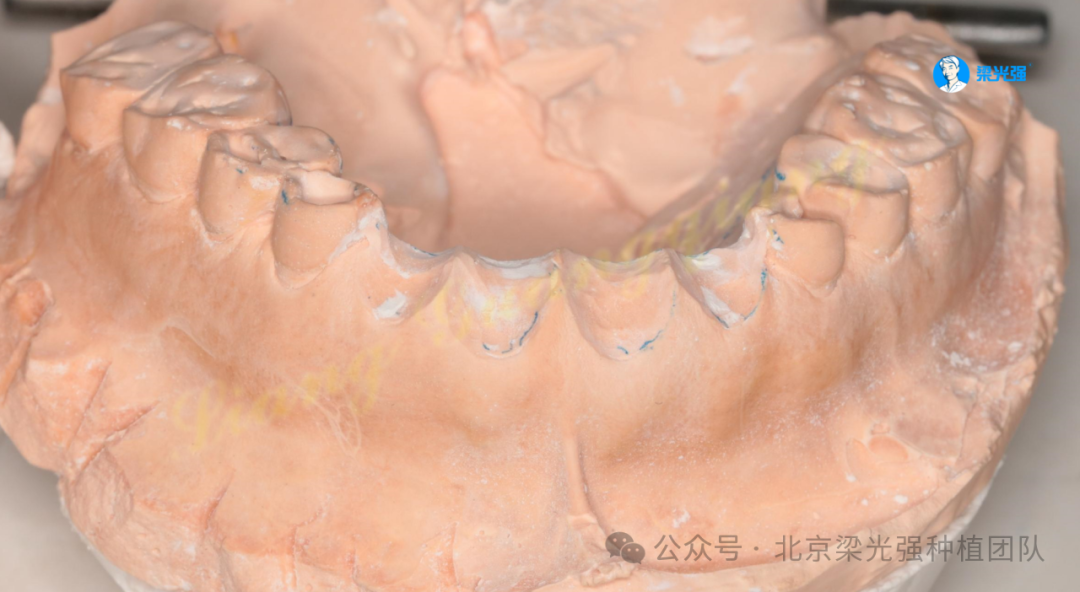

根据抬高的颌关系上颌架制作颌垫和临时牙(由于咬合关系,同时骨密度小,扭力不足,无法制作固定的临时修复)。

图片